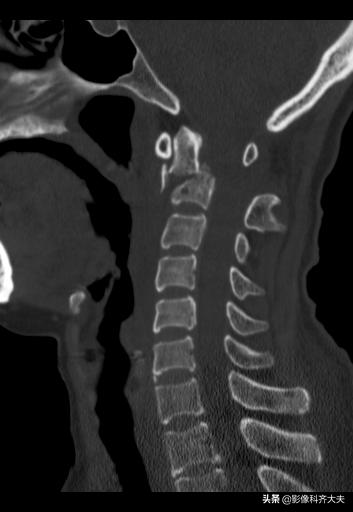

枢椎骨折

枢椎骨折矢状面重建

MRI矢状面枢椎骨折压迫脊髓

颈椎滑脱骨折脊髓挫伤